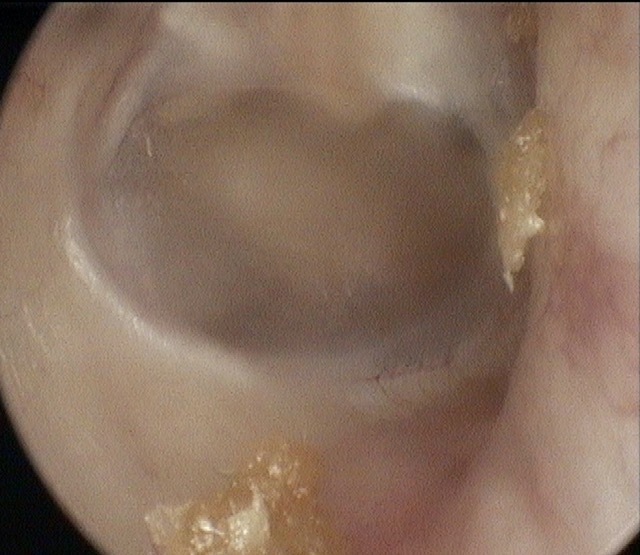

Perforation